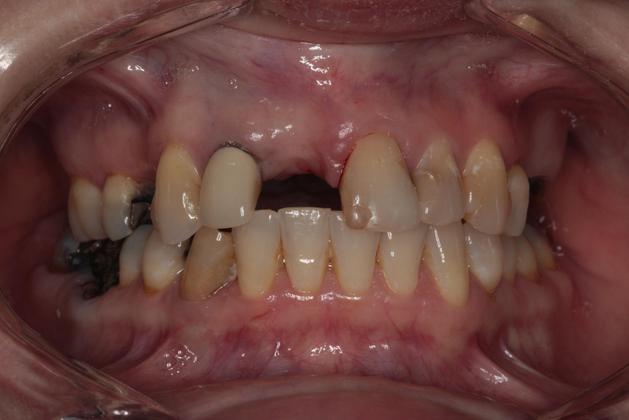

While the health benefits of restorative dentistry are clear, patients can also enjoy a higher level of self-esteem after receiving treatment. By addressing missing or damaged teeth, many patients achieve a healthier-looking smile that makes them feel more confident.

"I'm 100% Satisfied"

I am so pleased with my implants. Dr. Collier is excellent and has great bedside manner. His staff and his assistants are awesome. He wanted everything to be perfect even if that meant having an extra visit. I was very impressed with his credentials when I was doing my research for an implant specialist and I’m glad that I chose Southern Dental Implant Center.

View On GoogleHave been going to Dr. Collier for 10 years. He really cares . I had an emergency problem, and even though he was booked for the day, he made sure to work me into the schedule. I’ve had quite a bit of restorative dentistry in past 10 years, and couldn’t be happier with the outcome Dr . Collier is a perfectionist when it comes to making things look great. He has always made sure that I was 100% satisfied with the work he performed.